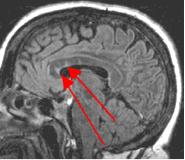

Fig. 1

By turning CSF dark, bright periventricular lesions such as MS plaques become much more conspicuous. Fig. 1 shows a typical T2-weighted axial image of the brain in which CSF in the ventricles appears bright. A lesion on the right is present (red arrow) that is also bright similar to CSF. Fig. 2 is a corresponding FLAIR image showing an obvious bright MS plaque (white arrow) against a background of dark CSF and gray parenchyma with additional more subtle lesions.